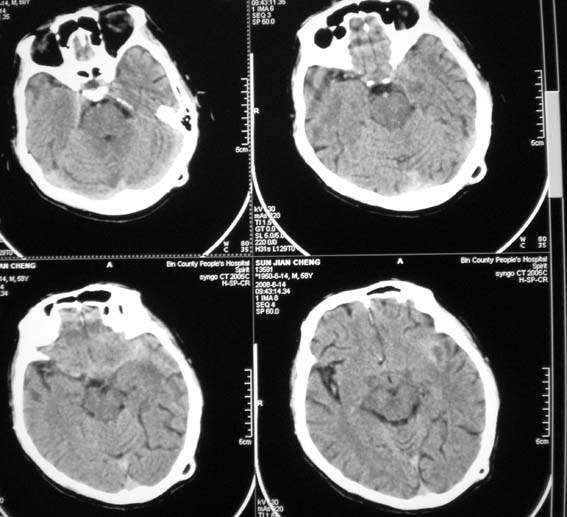

以下是引用随光逐影在2008-6-15 17:27:00的发言:[br]1)脑积水引流术后导管留置。2)蛛网膜下腔出血。3)左侧基底节区及左侧额叶多发脑腔隙灶。4)脑萎缩。

以下是引用dyqct在2008-6-15 10:32:00的发言:[br]支持:1、左侧外侧裂池密度增高,考虑出血。[br] 2、左侧基底节区脑软化灶。